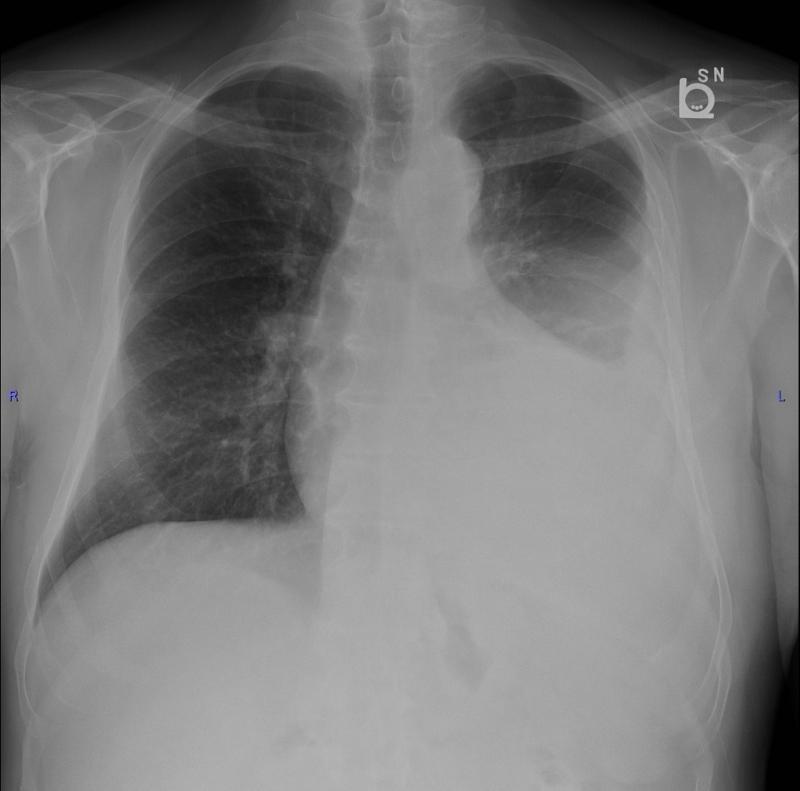

- Местные симптомы: связаны непосредственно с увеличением лимфоузлов. Например, увеличение лимфоузлов в грудной клетке (медиастинальных) может вызывать кашель, одышку или чувство сдавления за грудиной.

- Лучевая диагностика: для определения стадии заболевания и оценки распространенности процесса используются методы визуализации. Основным методом сегодня является позитронно-эмиссионная томография, совмещенная с компьютерной томографией (ПЭТ/КТ). Этот метод позволяет выявить все очаги опухолевой активности в организме, даже самые маленькие.